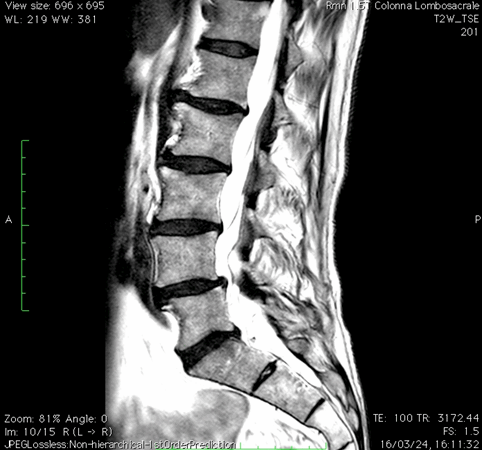

Risonanza magnetica lombare pre-operatoria

Intervento chirurgico eseguito:

PROCEDURA PLIF: POSTERIOR LUMBAR INTERBODY FUSION

Stabilizzazione vertebrale percutanea L4-L5 + introduzione di cage intersomatica PLIF Radiografia lombare post-operatoria